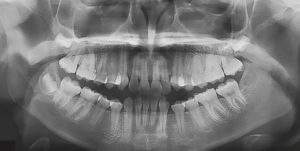

Agenesia de incisivos mandibulares y tratamiento ortodóncico

Para comenzar la primera semana de agosto traemos un artículo llamado Agenesis of Mandibular Incisors and Orthodontic Management Agenesis of Mandibular Incisors and Orthodontic Management, publicado en el Taiwanese Journal of Orthodontics. El artículo trata sobre el manejo de la agenesis de los incisivos mandibulares. Explica el abordaje de esta condición, considerando diferentes estrategias para … Sigue leyendo Agenesia de incisivos mandibulares y tratamiento ortodóncico